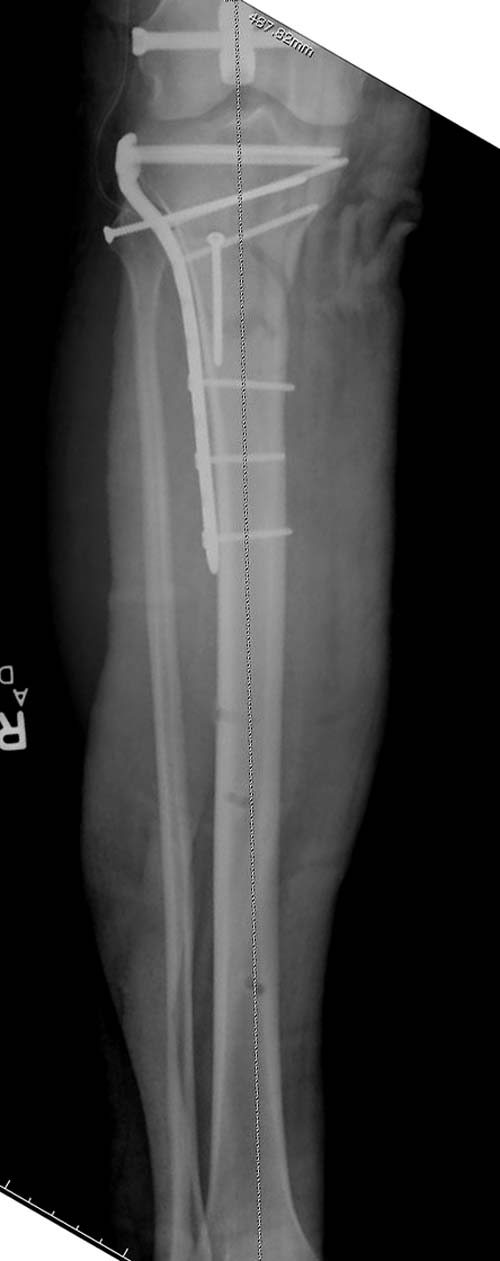

Похожий случай, вчера прооперировали. Непрямая репозиция, малоинвазивный остеосинтез без обнажения зоны перелома.

здравствуйте! создается впечатление о фиксации перелома голени в варусном положении

Согласен, на снимке “создается впечатление о фиксации перелома голени в варусном положении”, но на других отсутствует..